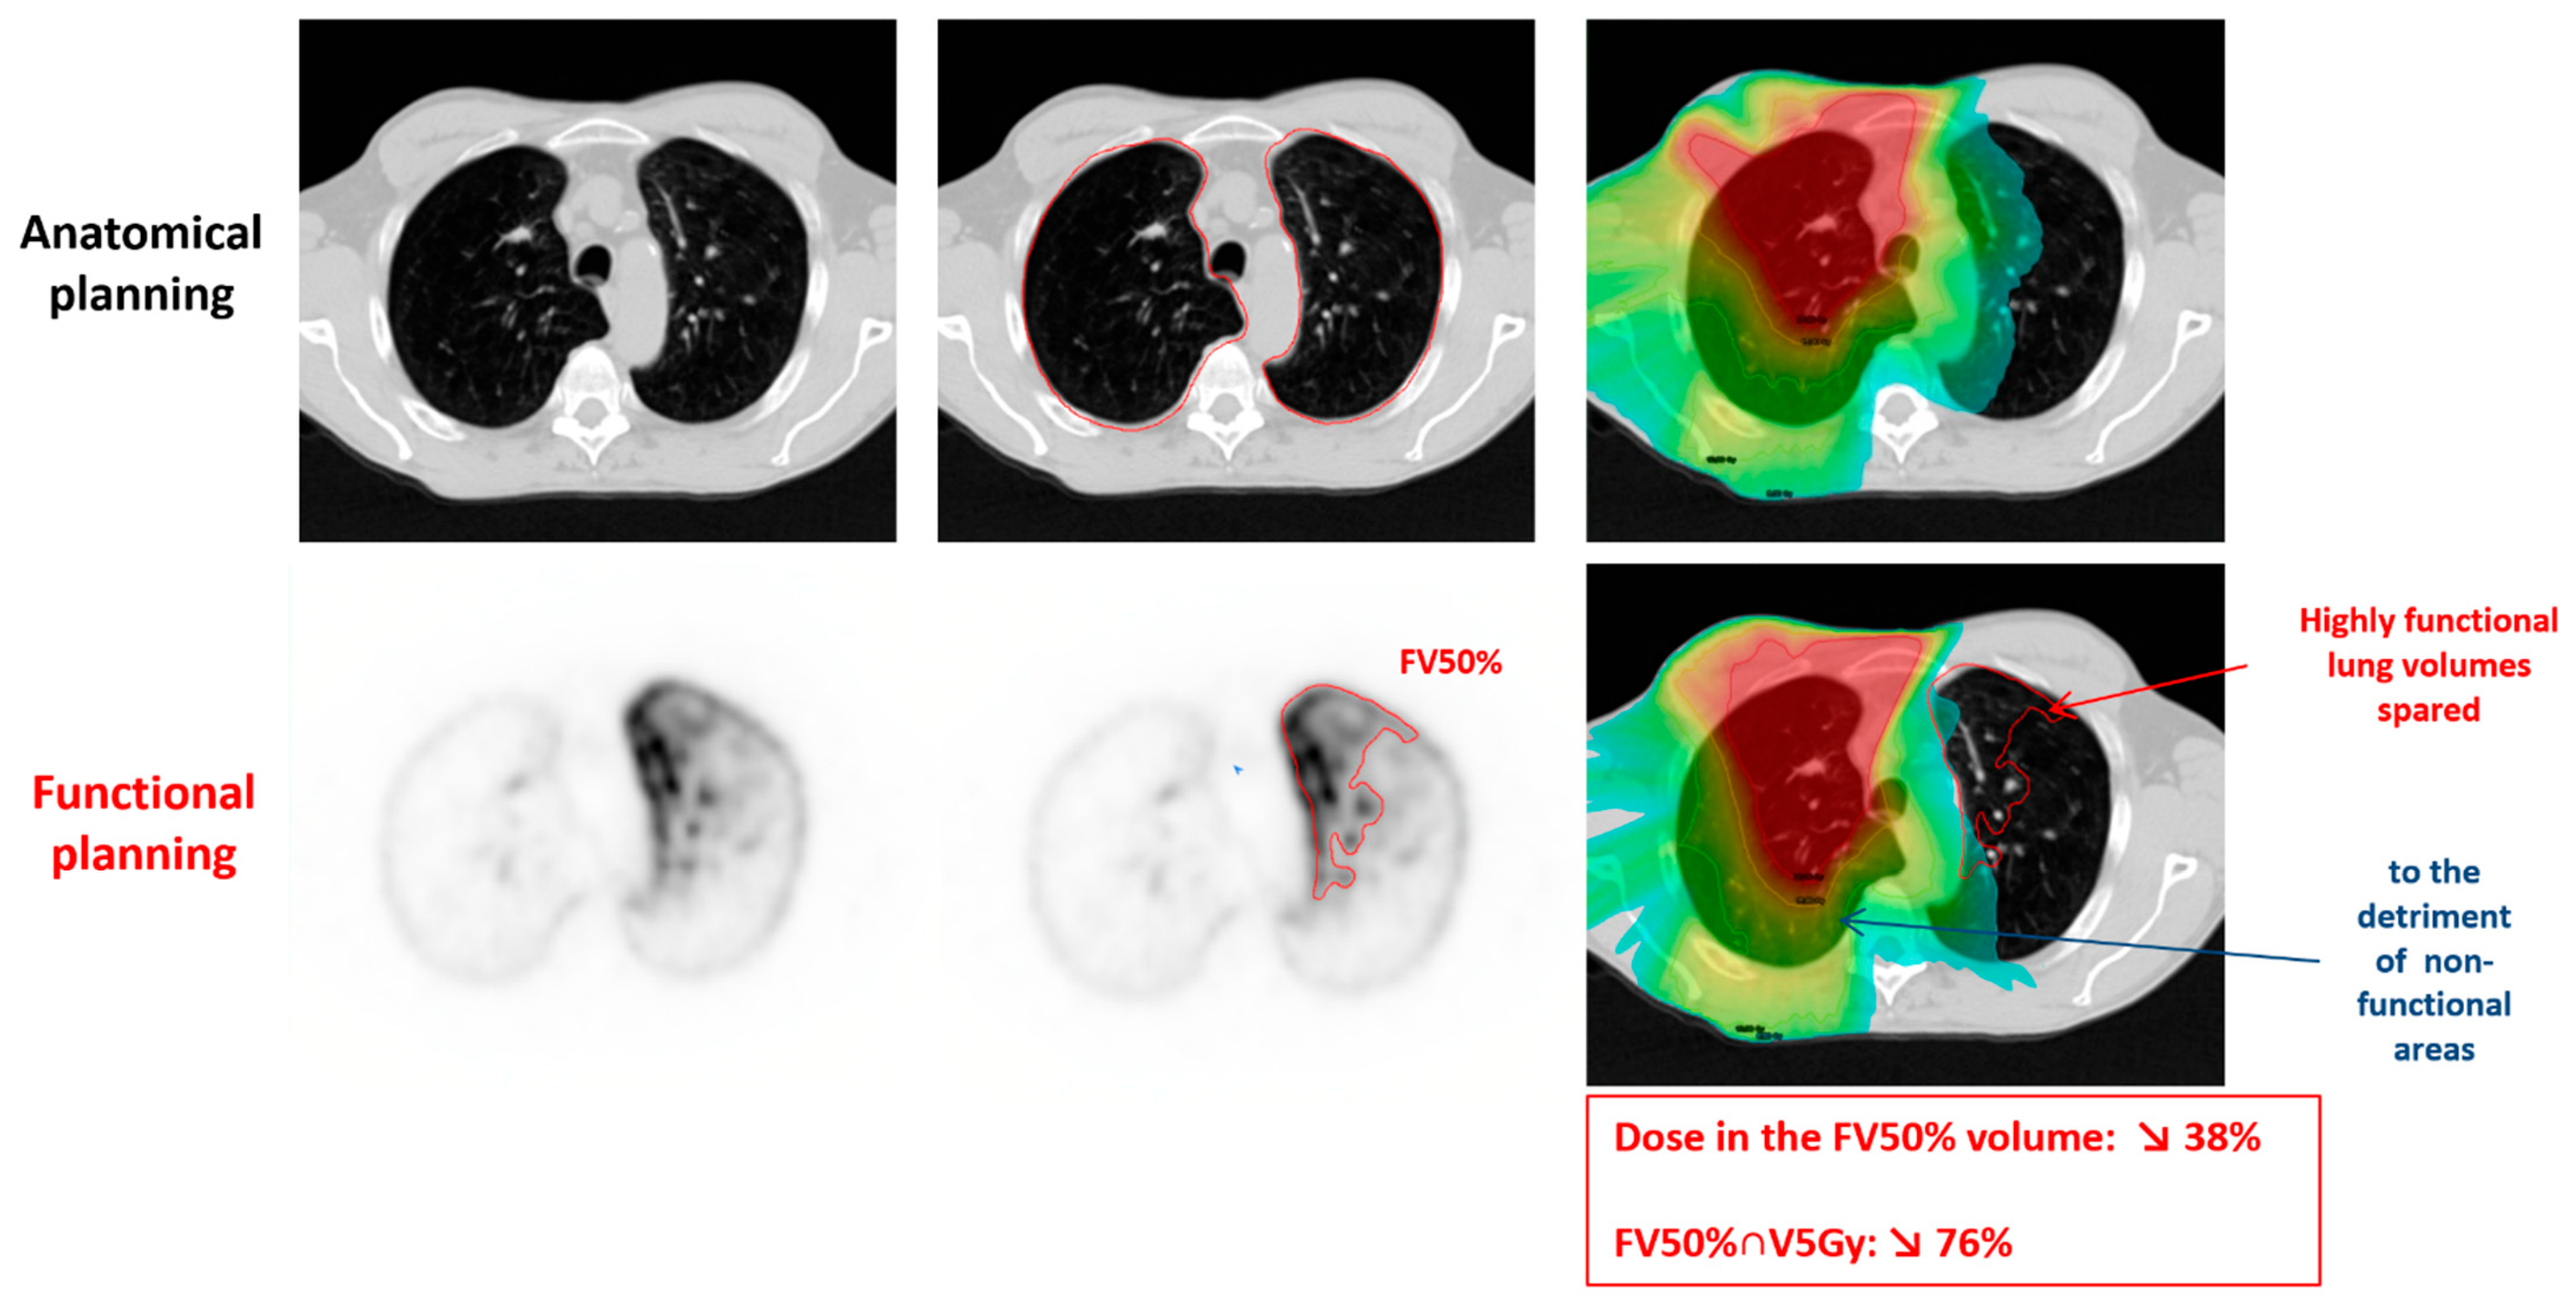

| FV50% | 3.1 (0.2–12.7) | 3.0 (0.2–12.4) | −0.2 (−1.1 to 0.1) | −8.0 (−43.0 to 1.2) | <0.0001 |

| FV70% | 3.3 (0.3–10.7) | 3.0 (0.3–10.4) | −0.2 (−0.8 to 0.1) | −7.1 (−34.3 to 1.2) | <0.0001 |

| FV90% | 3.0 (0.6–9.9) | 2.8 (0.6–9.5) | −0.2 (−0.8 to 0.2) | −5.7 (−22.3 to 4.4) | <0.0001 |

| Anatomical | 2.7 (0.8–7.5) | 2.5 (0.7–7.2) | −0.1 (−0.5 to 0.3) | −4.7 (−15.8 to 8.5) | <0.0001 |

| FV50% | V5Gy | 16.1% (0.1% to 48.2%) | 14.0% (0% to 46.8%) | −1.4% (−8.4% to 4.5%) | −11.4% (−100% to 19.2%) | <0.0001 |

| V10Gy | 8.6% (0% to 41.2%) | 7.7% (0% to 40.0%) | −0.8% (−5.1%to 0.9%) | −12.5% (−99.9% to 6.5%) | <0.0001 | |

| V15Gy | 5.5% (0.0% to 30.5%) | 4.7% (0.0% to 29.5%) | −0.5% (−5.3% to 0.3%) | −10.6% (−90.4% to 7.5%) | <0.0001 | |

| V20Gy | 3.6% (0.0% to 22.6%) | 3.3% (0.0% to 21.8%) | −0.3% (−2.9% to 0.3%) | −9.2% (−100% to 9.2%) | <0.0001 | |